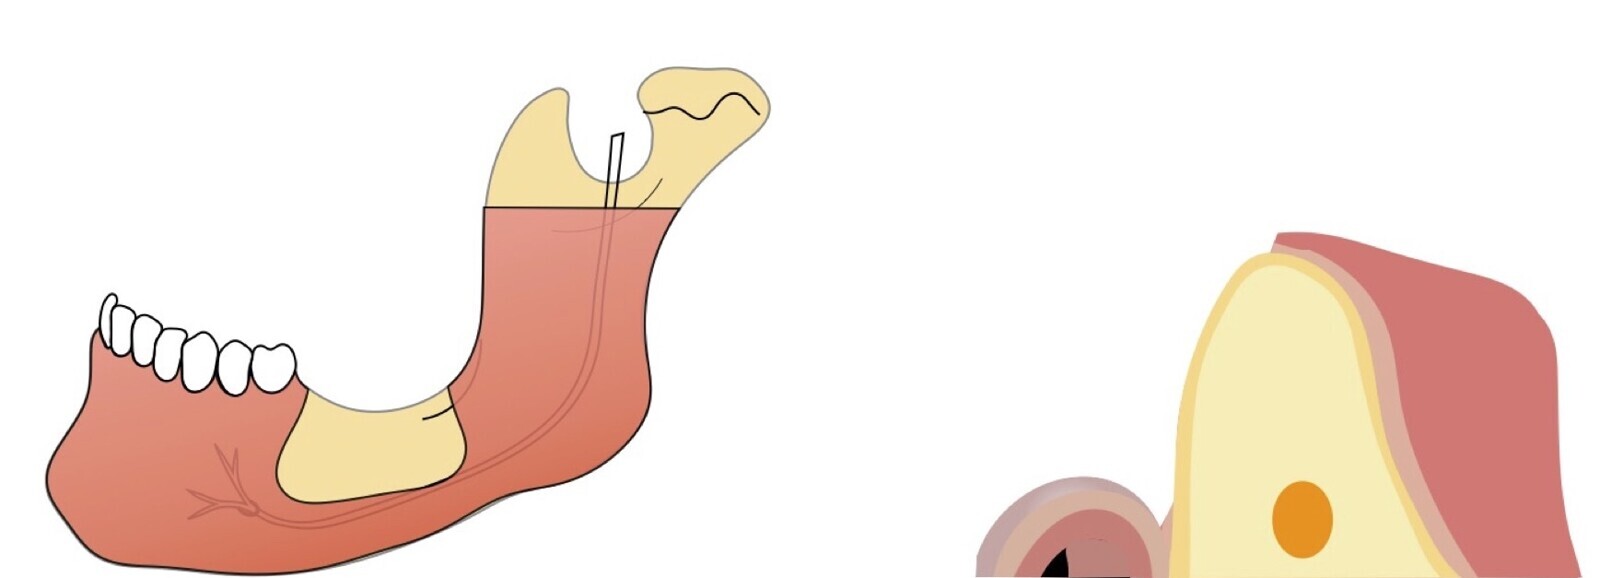

Si la zona donadora es la rama mandibular, una vez realizado el decolado (Figura 4), se procede a realizar la osteotomía con los insertos de corte, según la accesibilidad se escoge el inserto angulado (Figura 5) o recto (Figura 6). Iniciamos con el corte horizontal que va desde la zona retromolar hacia mesial hasta unos 5 mm próximos a la última pieza dentaria, este corte se realiza con el inserto recto, luego se realizan osteotomías verticales. Finalmente, se realiza la osteotomía horizontal inferior con el inserto angulado del lado correspondiente, pero se debe determinar previamente en la tomografía la distancia al nervio dentario inferior, para evitar dañarlo por proximidad.

La osteotomía con insertos de piezoeléctrico nos permite un corte más definido con menor pérdida de hueso residual, ya que los insertos son extremadamente finos (0.25, 0.40 y 0.50 mm) (Figuras 7 y 8).